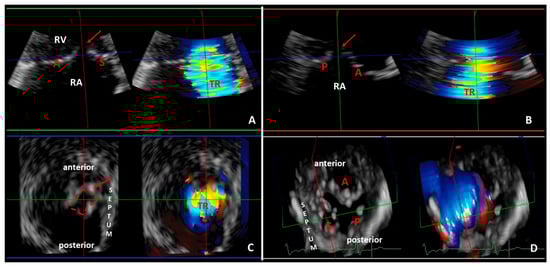

- Lancellotti, P.; Pibarot, P.; Chambers, J.; La Canna, G.; Pepi, M.; Dulgheru, R.; Dweck, M.; Delgado, V.; Garbi, M.; Vannan, M.A.; et al. Multi-modality imaging assessment of native valvular regurgitation: An EACVI and ESC council of valvular heart disease position paper. Eur. Heart J. Cardiovasc. Imaging 2022, 23, e171–e232. [Google Scholar] [CrossRef]

- Badano, L.P.; Hahn, R.; Rodríguez-Zanella, H.; Araiza Garaygordobil, D.; Ochoa-Jimenez, R.C.; Muraru, D. Morphological Assessment of the Tricuspid Apparatus and Grading Regurgitation Severity in Patients with Functional Tricuspid Regurgitation: Thinking Outside the Box. JACC Cardiovasc. Imaging 2019, 12, 652–664. [Google Scholar] [CrossRef] [PubMed]

- Lancellotti, P.; Moura, L.; Pierard, L.A.; Agricola, E.; Popescu, B.A.; Tribouilloy, C.; Hagendorff, A.; Monin, J.L.; Badano, L.; Zamorano, J.L. European Association of Echocardiography recommendations for the assessment of valvular regurgitation. Part 2: Mitral and tricuspid regurgitation (native valve disease). Eur. J. Echocardiogr. 2010, 11, 307–332. [Google Scholar] [CrossRef] [PubMed]

- Velayudhan, D.E.; Brown, T.M.; Nanda, N.C.; Patel, V.; Miller, A.P.; Mehmood, F.; Rajdev, S.; Fang, L.; Frans, E.E.; Vengala, S.; et al. Quantification of tricuspid regurgitation by live three-dimensional transthoracic echocardiographic measurements of vena contracta area. Echocardiography 2006, 23, 793–800. [Google Scholar] [CrossRef] [PubMed]

- Chen, T.E.; Kwon, S.H.; Enriquez-Sarano, M.; Wong, B.F.; Mankad, S.V. Three-dimensional color Doppler echocardiographic quantification of tricuspid regurgitation orifice area: Comparison with conventional two-dimensional measures. J. Am. Soc. Echocardiogr. 2013, 26, 1143–1152. [Google Scholar] [CrossRef]

- Song, J.M.; Jang, M.K.; Choi, Y.S.; Kim, Y.J.; Min, S.Y.; Kim, D.H.; Kang, D.H.; Song, J.K. The vena contracta in functional tricuspid regurgitation: A real-time three-dimensional color Doppler echocardiography study. J. Am. Soc. Echocardiogr. 2011, 24, 663–670. [Google Scholar] [CrossRef]

- Chouchani, M.; Michaelsen, J.; Langenbrink, L.; Piatkowski, M.; Altiok, E.; Hoffmann, R. Quantification of tricuspid regurgitation area by 3-dimensional color Doppler echocardiography considering different clinical settings. Echocardiography 2020, 37, 1120–1129. [Google Scholar] [CrossRef] [PubMed]

- de Agustin, J.A.; Viliani, D.; Vieira, C.; Islas, F.; Marcos-Alberca, P.; Gomez de Diego, J.J.; Nuñez-Gil, I.J.; Almeria, C.; Rodrigo, J.L.; Luaces, M.; et al. Proximal isovelocity surface area by single-beat three-dimensional color Doppler echocardiography applied for tricuspid regurgitation quantification. J. Am. Soc. Echocardiogr. 2013, 26, 1063–1072. [Google Scholar] [CrossRef]

- Abudiab, M.M.; Chao, C.J.; Liu, S.; Naqvi, T.Z. Quantitation of valve regurgitation severity by three-dimensional vena contracta area is superior to flow convergence method of quantitation on transesophageal echocardiography. Echocardiography 2017, 34, 992–1001. [Google Scholar] [CrossRef]